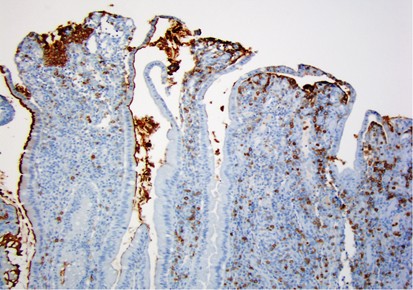

Specimens from patients with documented inflammatory bowel disease had a higher rate of patchy CD10 staining as well as a larger amount of epithelium that was CD10-negative, with 22/34 (65%) losing areas of CD10 positivity. Specifically, 7/16 (44%) ileal pouches, 6/8 (75%) backwash ileitis, and 9/10 (90%) Crohn's ileitis cases had patchy CD10 loss (Figures 3 and 4). All of the cases in which staining was patchy had active mucosal inflammation, and the pattern of loss ranged from scattered areas of CD10 negativity to long, contiguous stretches of CD10-negative epithelium, the latter is most common in backwash ileitis cases (Figure 5). The amount of epithelium with loss of staining varied from 20 to 90% (mean 55%) in backwash ileitis, 10 to 60% (mean 36%) in ileal pouches, and 10 to 80% (mean 32%) in Crohn's ileitis. In cases with mucosal ulcers, loss of CD10 staining was accentuated in the intact epithelium immediately surrounding the ulcers. Summary results for ileal specimens by diagnostic group are shown in Table 1.

CD10 staining in Crohn's ileitis. This case had an estimated 70% overall loss of CD10 positivity. Note the patchy nature of the staining, with strong positivity (left) juxtaposed with large negative areas (right). Inset shows high-power view. Note that terminal bar appears to be present even in CD10-negative areas (arrow).